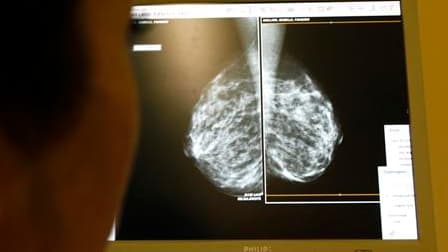

Le cancer de la prostate chez l'homme et du sein chez la femme sont les plus fréquents en France, où le cancer du poumon fait aussi des ravages. /Photo d'archives/REUTERS/Eric Gaillard

Chez la femme, le cancer du sein reste le plus fréquent avec 52.600 nouveaux cas prévus en 2010. C'est aussi le plus meurtrier, avec 11.300 décès prévus, même si "le taux de mortalité diminue en France depuis près de 15 ans", note l'InVS.